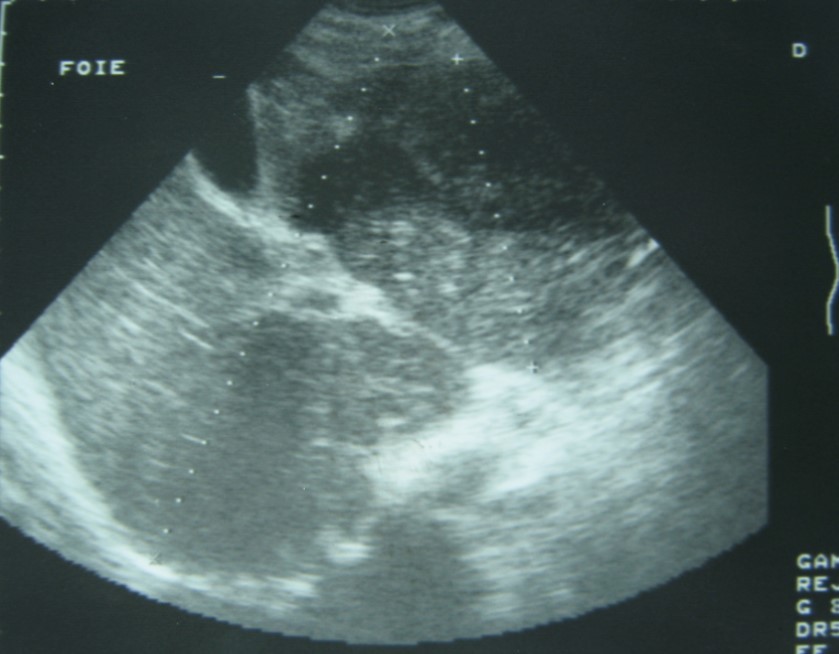

Laboratory analysis showed hemoglobin, 10.9 g/dL; white blood cell count, 9,800 cells/mm3, serum albumin, serum total bilirubin, alanine aminotransferase, aspartate aminotransferase, prothrombin time, hepatitis B surface antigen, and antibodies to hepatitis C, serum alpha-fetoprotein (AFP), carcinoembryonic antigen and carbohydrate antigen 19-9 (CA 19-9) were within normal range. Blood cultures were negative. Chest x-ray was normal. Ultrasound of abdomen showed a 10 cm hypoechogenic lesion in left liver (Figure 1). An abdominal CT showed a well-defined heterogeneous mass situated in his left hepatic lobe measuring 10 cm × 7 cm (Figure 2, Figure 3). The lesion featured central necrosis, a hyper-dense rim and a mild enrichment from the arterial phase in the CT, The diagnosis of primary hepatic tumor was suspected. An ultrasonography-guided needle biopsy of the liver was scheduled in order to rule out malignancy and to have a complete diagnosis. Cytology demonstrated a tuberculosis granuloma, acid-fast bacilli culture was positive (Figure 4). Anti-tuberculous therapy including isoniazid, rifampin, ethambutol, and pyrazinamide were prescribed. The patient completed the 6-month course of medication with success. The patient’s appetite and body weight were restored to previous levels. One year after the completion of treatment, the patient remained completely asymptomatic with disease free.

Figure 1.Ultrasonography showing a 10 cm hypoechoic lesion

Imaging is useful for diagnosis. Abnormal chest x-rays demonstrating pulmonary tuberculosis can help for diagnosis. Our patient presented with no evidence of active pulmonary disease and the ultrasonography showed a hypoechoic rim and solitary lesion. In theses cases, it is difficult to differentiate them from carcinoma 11.